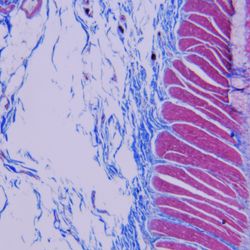

Squamous cell carcinoma

AI is on the rise worldwide—and the field of histology is no exception to this trend. In a new study from Japan, researchers sought to improve the ability of deep learning models to provide diagnostic histopathology support.1 To do this, they asked pathologists to prepare oral squamous cell carcinoma samples, which were then digitized, labeled, and presented to existing convolutional neural networks VGG16 and ResNet50. Though several sets of parameters were tested, the highest-performing combination was VGG16 used with a learning rate scheduler and the spectral angle mapper optimizer.